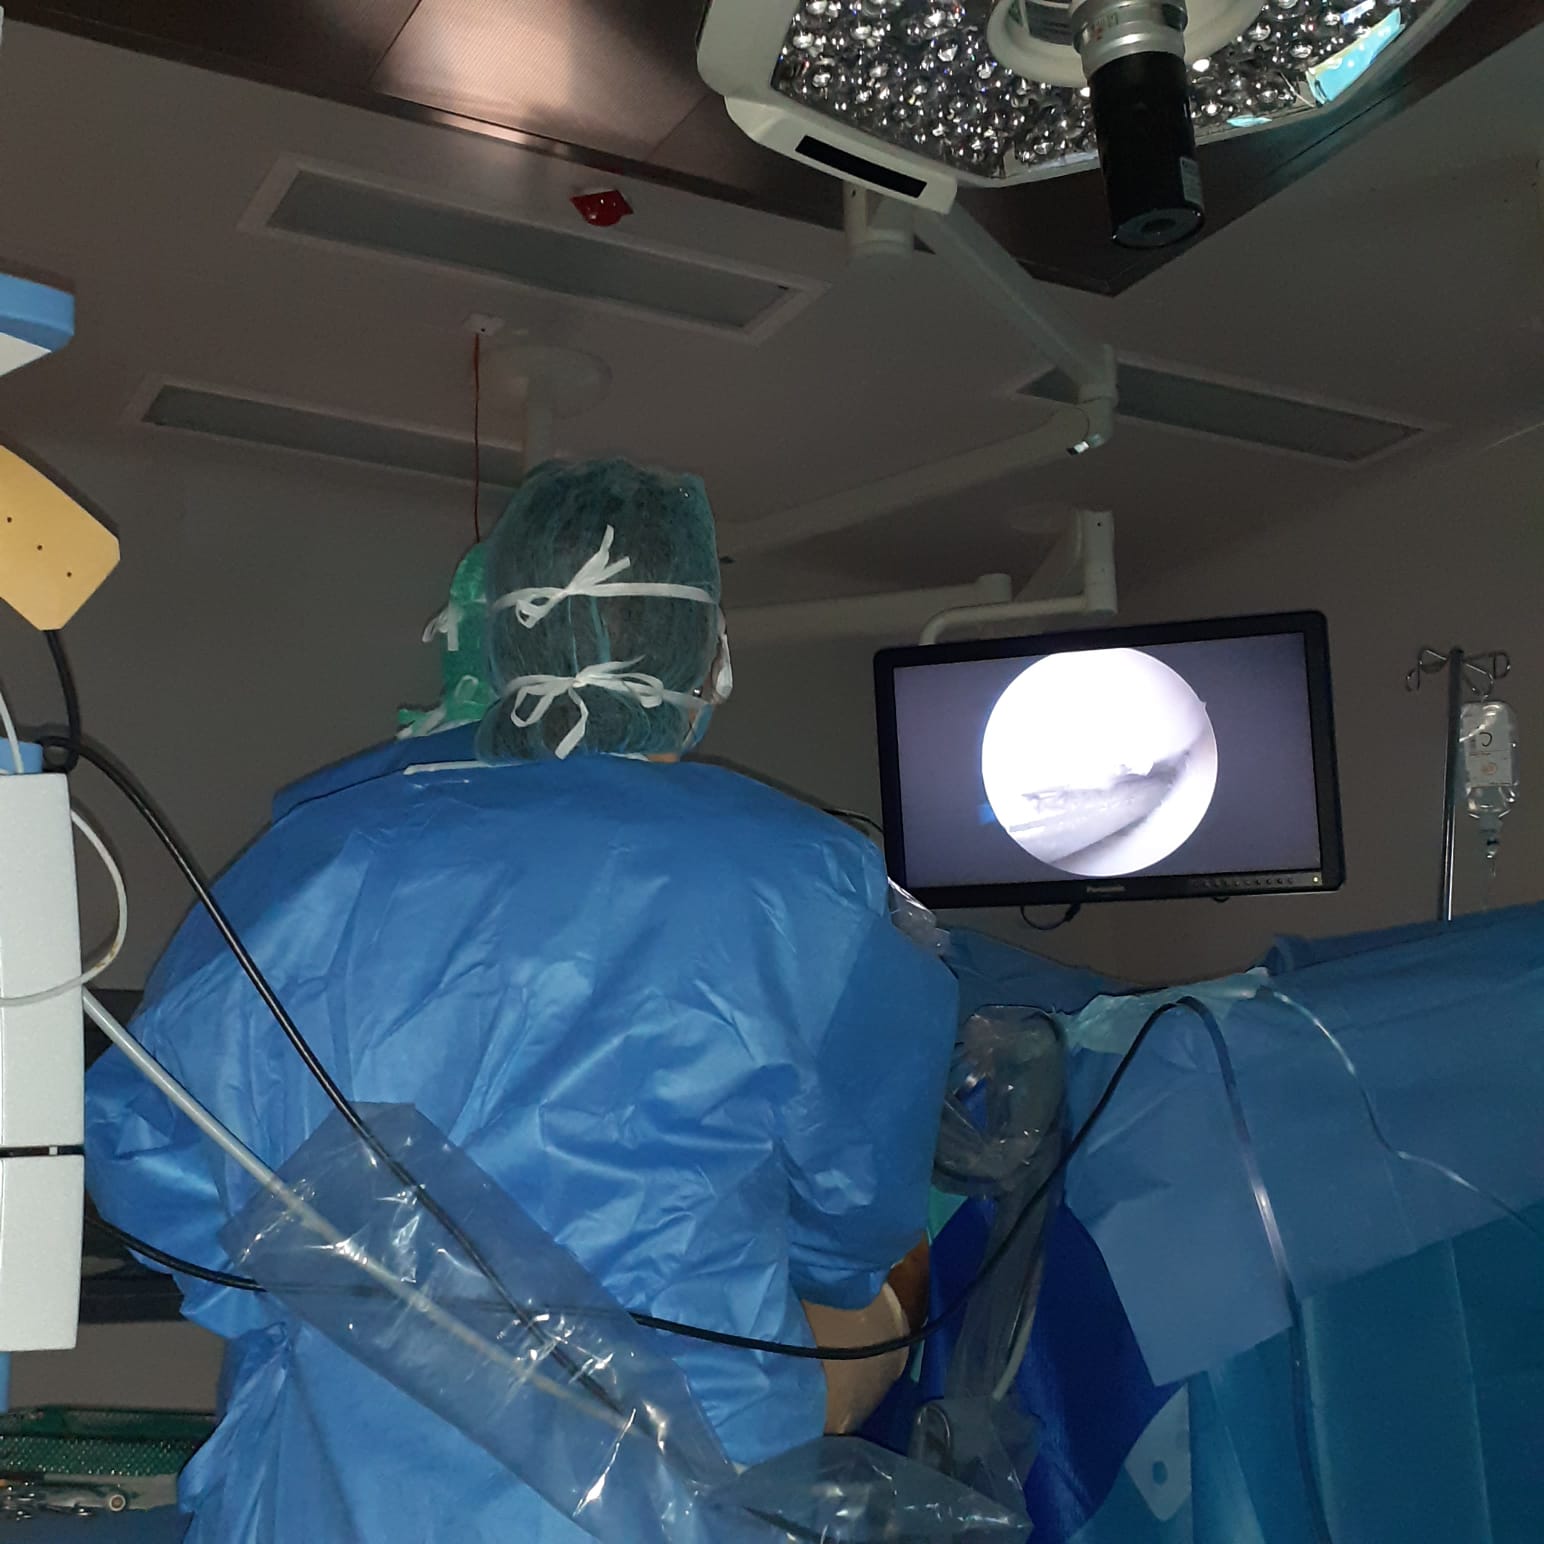

Citește mai multArtroscopia-tratamentul pentru traumatismul genunchiului

Artroscopia, tratamentul pentru traumatismul genunchiului, interventie minim invaziva Trateaza la timp leziunile interne ale genunchiului [...]